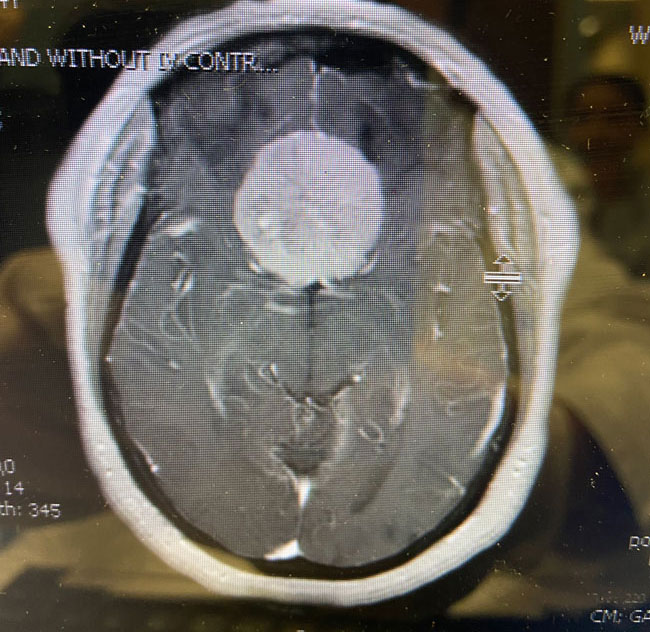

The patient underwent a bifrontal craniotomy and near total removal of the tumor. Because the frontal sinuses were small, it was possible to perform the craniotomy without violating the frontal sinuses. The tumor was removed nearly completely except for a small portion that was stuck to the optic nerves and the anterior communicating artery complex (Figure 2). Postoperatively, the patient immediately noted that her vision had been restored to normal. She was discharged on postoperative day 2. The small remaining tumor will be followed, and may be treated with stereotactic radiosurgery in the future.

Meningiomas can arise from any meningeal tissue within the brain or spinal canal. They are almost all benign tumors. This particular tumor arose from the planum sphenoidale, the flat posterior midline part of the sphenoid bone, a region that forms part of the floor of the anterior cranial fossa. Sometimes these tumors can be removed safely in entirety, depending on how adherent the tumor is to the deep surrounding structures, in particular, the optic nerves, the optic chiasm, and the anterior communicating artery. In this case, the tumor was quite adherent to these most posterior and inferior structures, so it was decided not to risk dissecting this last remaining piece of tumor off these critical structures.